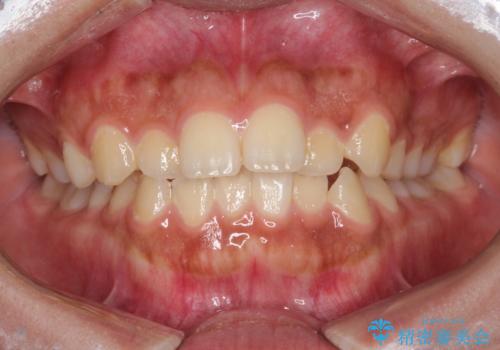

話しにくい歯並びの改善 抜歯矯正治療と前歯の審美治療

前歯の後戻りを部分矯正で整った歯並びへ

前歯のデコボコを治したい 費用を抑えた抜歯矯正

前歯をきれいに整えたい ワイヤー装置での非抜歯矯正

気になる八重歯を治したい ワイヤー装置での抜歯矯正